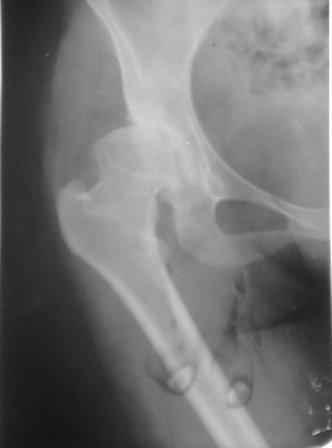

Типичная концовка проигнорированного диспластического состояния сустава. Дисплазия тазобедренного сустава часто встречающаяся патология у жителей Центральной Азии вследствие тугого пеленания в детстве. Традиционно ребенок находится в течение дня в так называемой кроватке "бешик", удобной в быту, но она впоследствии приводит к недоразвитию тазобедренного сустава.

Данный сустав в начальной стадии разрушения, но все-таки я бы сделал обзорный таз и отдельные снимки сустава в 30 градусной абдукции и аддукции. Также снимки с внутренней и наружной ротацией для оценки состояния головки бедра.